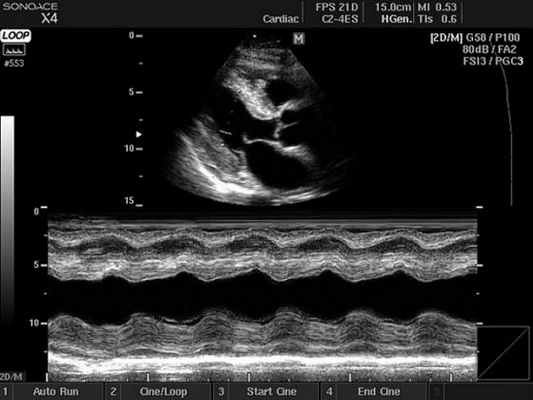

M-режим

M-режим (M – motion) – режим одномерного сканирования с получением развертки в реальном масштабе времени, который применяется для регистрации пространственного положения исследуемых объектов во времени (отслеживания движения исследуемых структур). Наиболее часто данный режим используется при кардиологических исследованиях совместно с B-режимом, где B-режим используют для навигации.

- Двухмерный (2D режим). На монитор выводится изображение сердца в разрезе (в двух измерениях). Данный способ является основным при визуализации этого органа, позволяет детально рассмотреть анатомические отклонения и аномальные движения миокарда, клапанов.

- М-режим (M-mode). Это «усеченный» вариант предыдущего, при котором используется для анализа только одномерное изображение. Основное внимание уделяется одной из линий 2D трассировки, что позволяет более детально исследовать движения створок клапанов и сердечной мышцы.